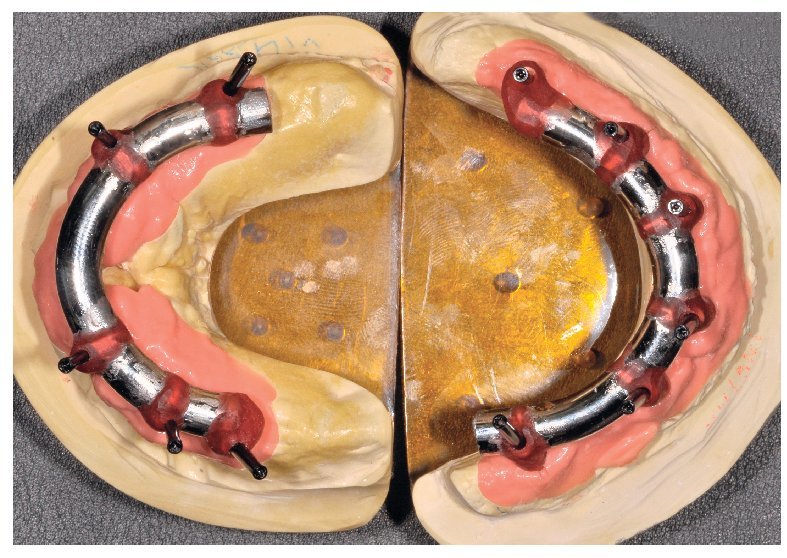

Figs. 101 y 102. Vista lateral de las estructuras atornilladas sobre los modelos.